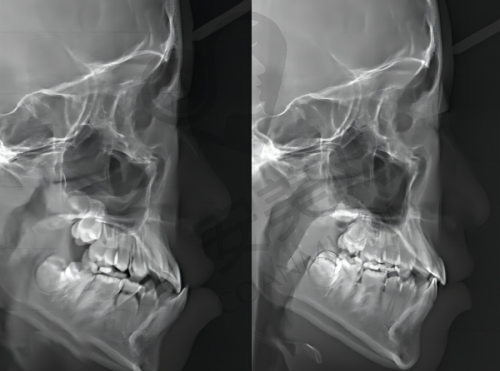

重庆牙博士口腔拥有一支经验多、技术不错的医疗团队。医生们经过专精的培训和长期的临床实践,熟练掌握登腾种植牙技术。在种植过程中,医生会运用精良的口腔CT等设备,对患者的口腔进行全方面、精细的检查和分析,制定个性化的种植方案。手术过程中,医生会严格遵循无菌操作原则,确保手术的安心和成功。同时,医院还引入了数字化种植技术,能够更严谨地控制种植体的植入位置和角度,提高种植的成功几率和成效。

患者到重庆牙博士口腔进行登腾种植牙,首先要进行全方面的口腔检查,包括口腔CT等检查项目,以了解患者的口腔状况和牙槽骨条件。医生会根据检查结果制定个性化的种植方案,并与患者充分沟通。确定方案后,患者需要进行术前准备,如清洁口腔、控制口腔炎症等。然后进行种植手术,将种植体植入牙槽骨内。术后患者需要遵循医生的嘱咐进行护理和修复,等待种植体与牙槽骨结合。待骨结合完成后,再安装基台和牙冠,至此种植牙手术全部完成。整个过程中,医生会密切关注患者的修复情况,确保手术的成功和患者的口腔健康。